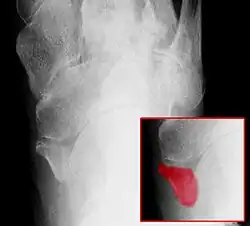

Os tibiale externum, Typ 2, (im kleinen Bild rot eingefärbt)

• Typ 2: Das Os tibiale externum ist dreieckförmig und bis zu 9 mm groß. Dieses hat eine Knorpelverbindung zum Kahnbein. Dieser Typ ist mit über 50 % der häufigste. Es handelt sich um eine unterbliebene Verschmelzung der Knochenkerne, aus denen sich das Kahnbein in der frühen Jugend bildet.